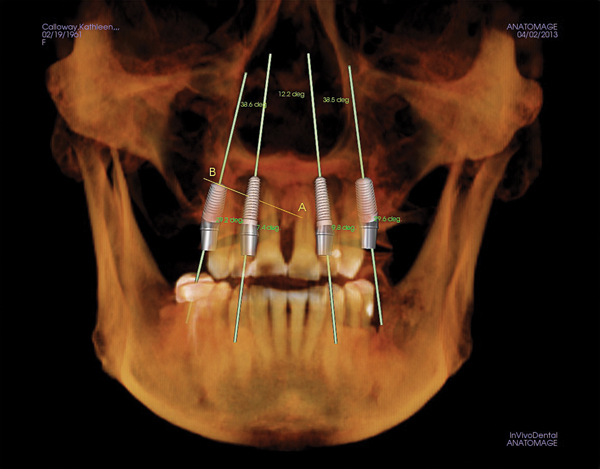

Figure 1 Traditional intraoral bitewing showing limited field of view (Fig 1) compared to the expanded view possible using CBCT (Fig 2).

Figure 2 Traditional intraoral bitewing showing limited field of view (Fig 1) compared to the expanded view possible using CBCT (Fig 2).

CBCT can also be used in this same manner to perform an even more common task, bitewing images, which are clinically indicated as often as every 18 to 24 months. For hygiene patients whose films require updating, CBCT offers a “patient-friendly” approach. Given that these films, which are usually performed intraorally, are often taken on an hourly basis in the typical general practice, the technology can be well utilized while also increasing comfort and satisfaction among patients. In addition, due to the expanded field of view that can be achieved with these extraoral CBCT images, they can often be more diagnostically valuable than images produced with an intraoral sensor (Figure 1 and Figure 2).